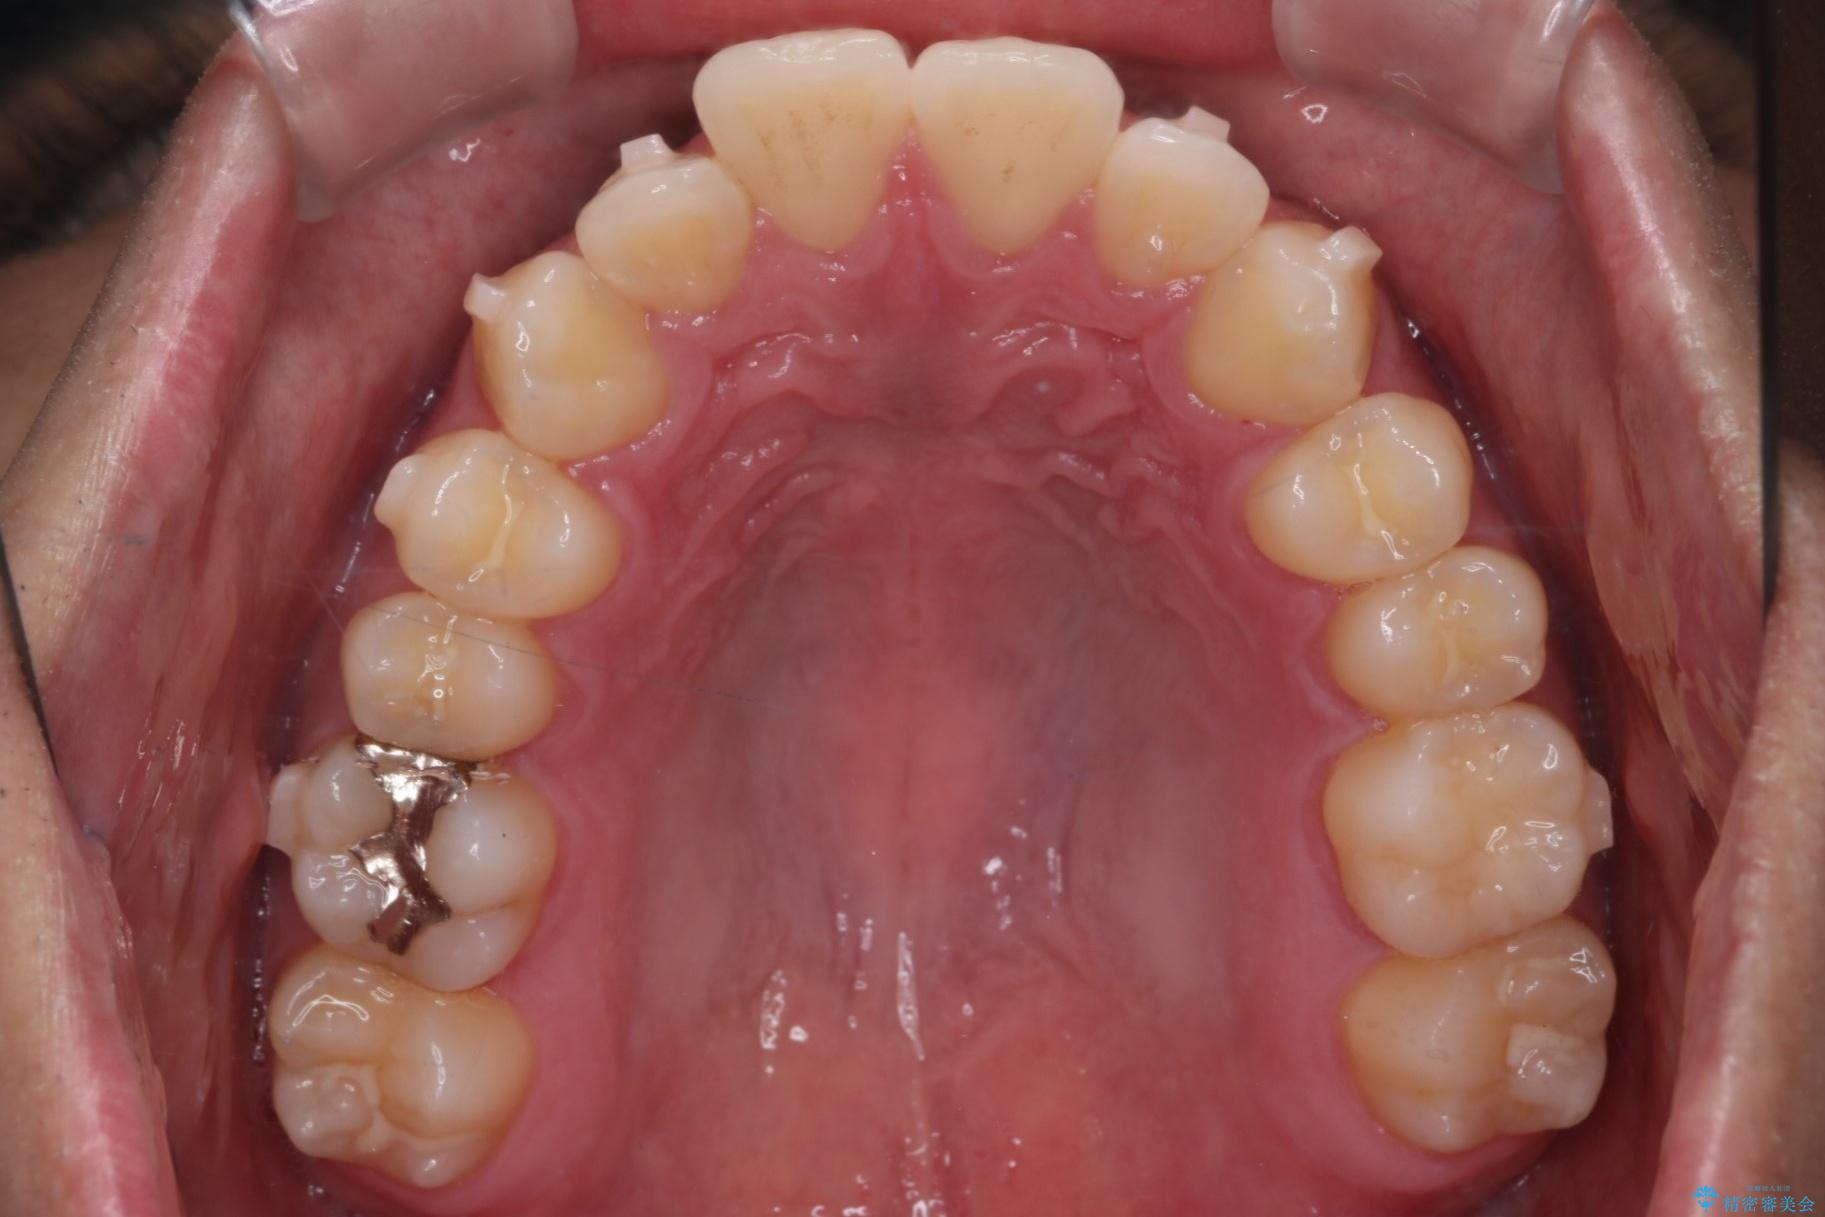

上の前歯が出ているのが気になるとご来院された患者様です。

治療計画

インビザラインでの治療を希望されました。

IPR(歯と歯の間を削る処置)を行うことで、前歯の位置とがたつき整える治療計画を立てました。